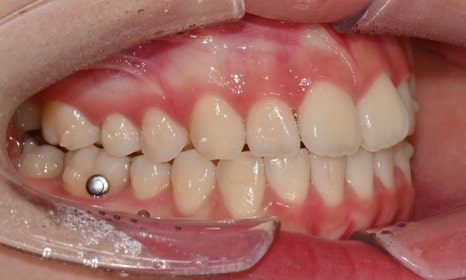

치료 시작 3개월 후 - 연세정원치과

치료 과정 중 환자는 장치 착용 시간을 매우 잘 지켜주었고, 내원 시마다 계획한 치아 이동이 비교적 정확하게 이루어지는 모습을 보였습니다. 이처럼 인비절라인 치료의 경우 환자의 협조도가 치료 결과에 큰 영향을 미치기 때문에, 이번 케이스에서는 환자의 성실한 장치 착용이 좋은 결과를 만드는 데 중요한 역할을 했다고 볼 수 있습니다.